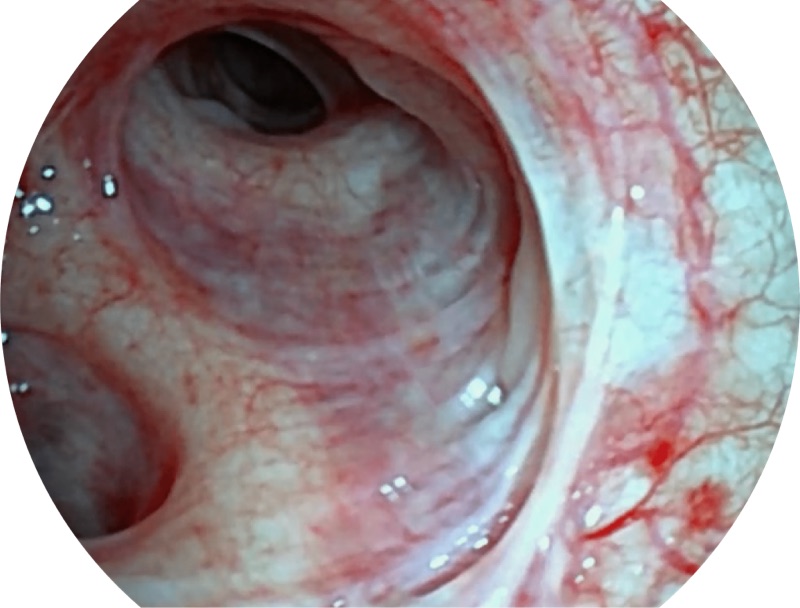

• 高清画质

帮助医生更加清晰地观察气管表面病灶